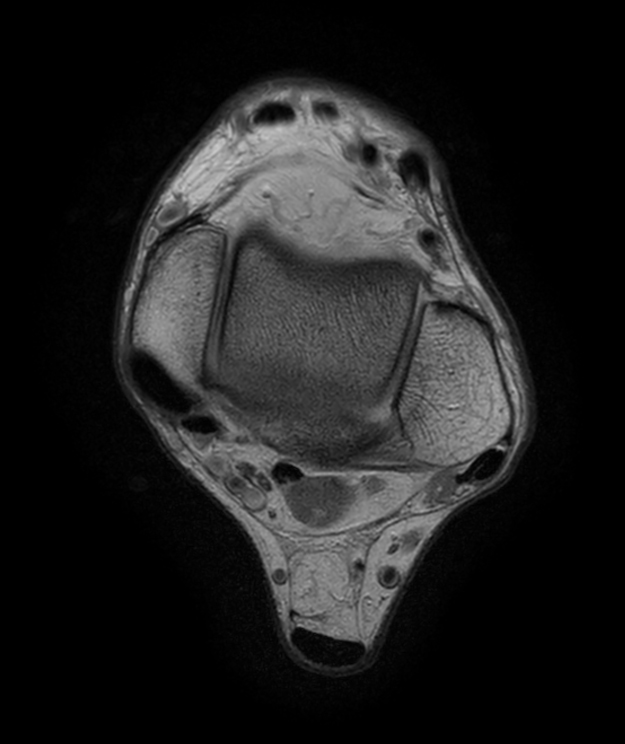

Ankle imaging with the dS 16ch FootAnkle coil

• Clinical Application